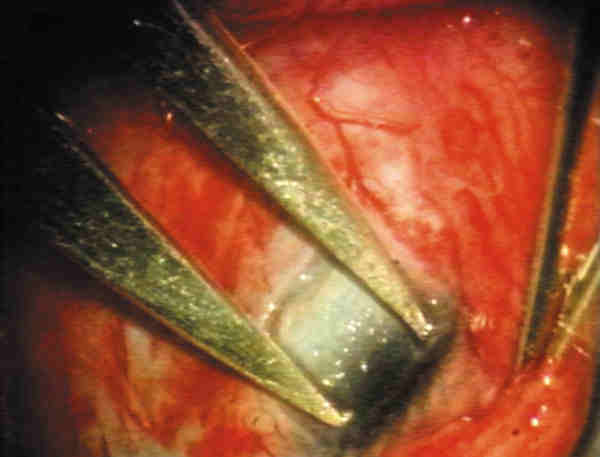

9. Trabeculectomía: Excisión del bloque interno de esclera-córnea-trabeculum. Recomendamos una sección de 2 ´ 2 mm de tejido (figura 2). Primeramente se perfila el lugar deseado, que debe comenzar en córnea y extenderse hasta la unión esclero-limbar (figura 3). La penetración en cámara anterior se realiza lentamente en una de las esquinas del cuadrado con el cuchillete quirúrgico. Se finaliza con tijera de Vannas (figura 4). La cámara anterior puede mantenerse con aire mientras se concluye el procedimiento.

08-02.jpg (15066 bytes)

Figura 2. Marcado de la zona de trabeculectomía.

08-03.jpg (13324 bytes)

Figura 3. Se perfila con el cuchillete de 22,5° el lugar de la trabeculectomía.